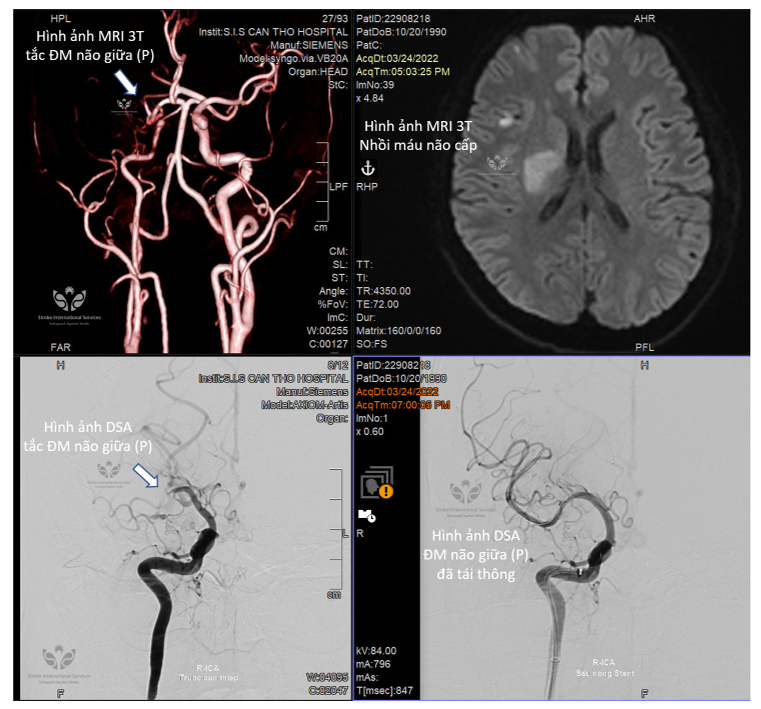

Chuyển viện kịp thời trong giờ vàng, bác sĩ trẻ bị đột quỵ hồi phục nhanh chóng

Một bác sĩ trẻ tại miền Tây khi mới phát hiện đột quỵ đã được chuyển viện nhanh chóng đến Bệnh viện Đa khoa Quốc tế S.I.S Cần Thơ và được can thiệp sớm. Chỉ sau 3 ngày, anh đã đi lại được. Sau khi xuất viện có thể trở lại làm việc bình thường.